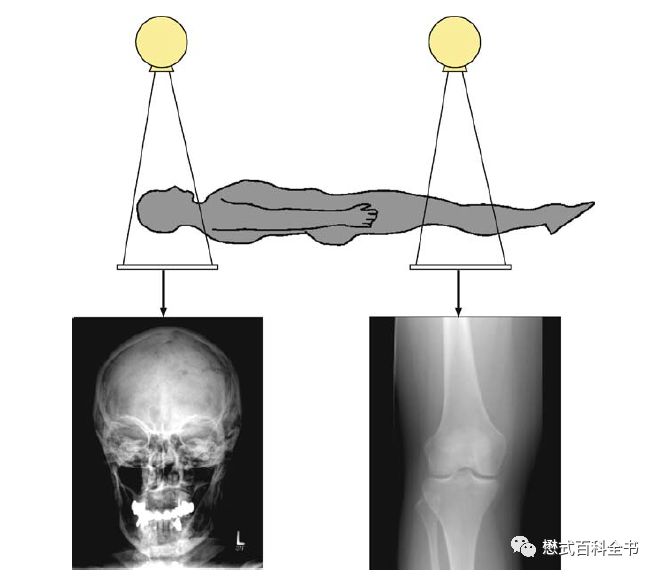

图6:传统的X线成像